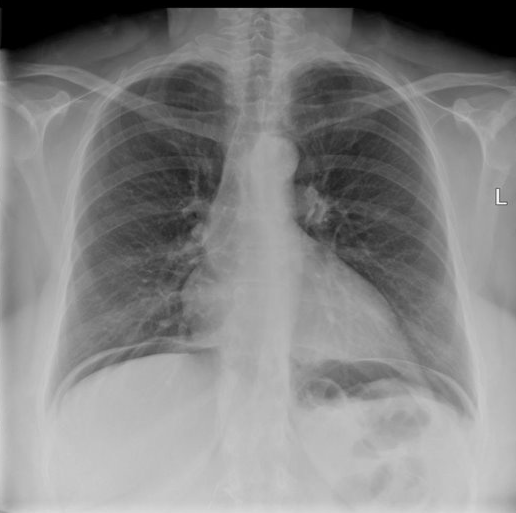

This shows?

pneumothorax